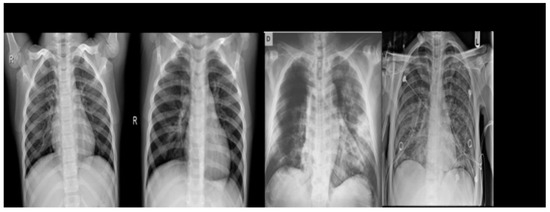

It has been created to support the research and development of artificial intelligence solutions for the automated diagnosis of COVID-19. This database contains a set of 1823 chest X-ray images, comprising 668 images of normal patients, 619 images of viral pneumonia cases and 536 images of patients with COVID-19 (show Figure 3).

Figure 3. Example of chest X-ray images from COVID CXR Image Dataset Research.

Algorithms 18 00210 g003